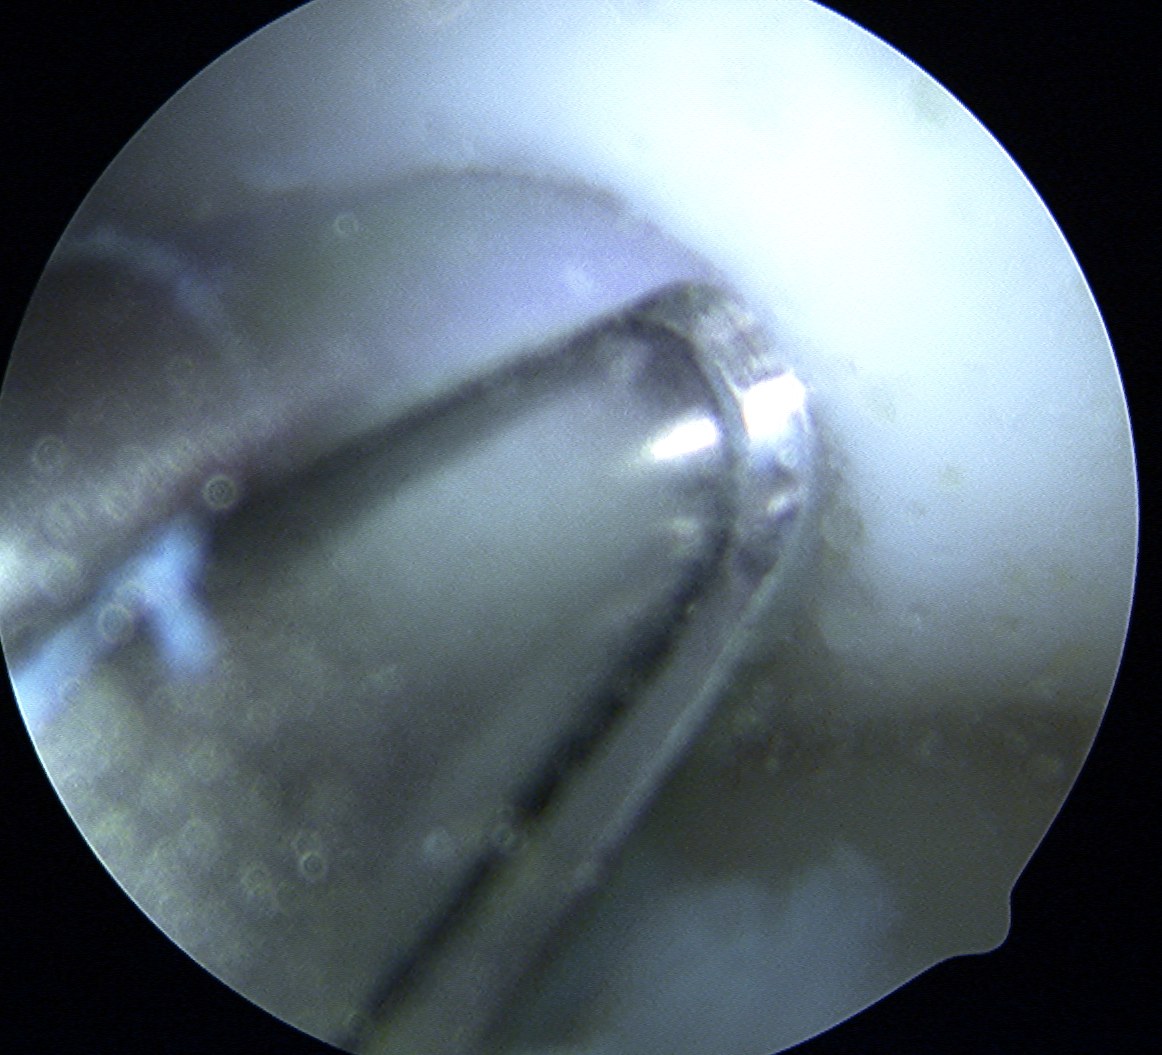

Harvest

- insert 4.5 mm chisel

- hammer to appropriate depth / 20 mm

- twist handle to remove